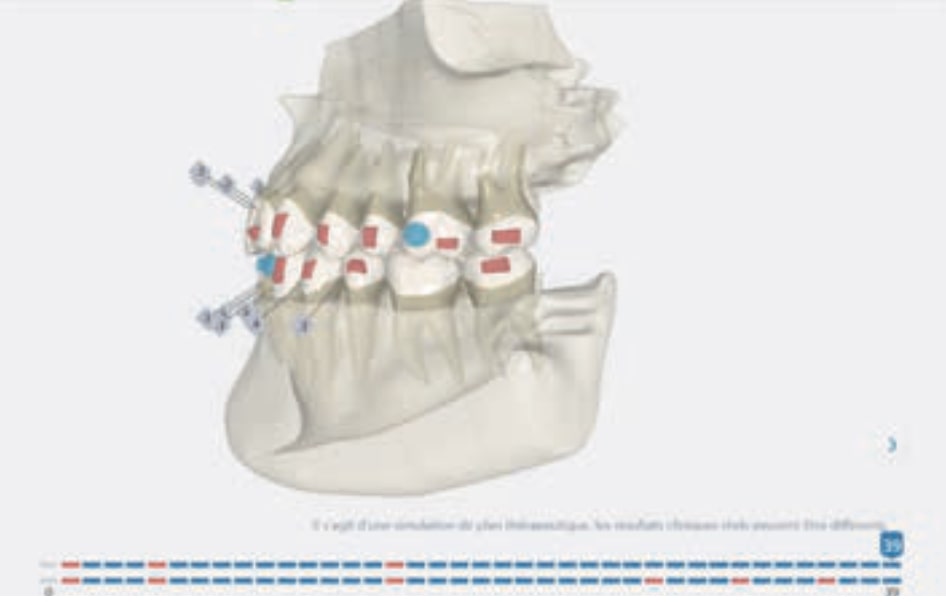

Protocoles and features A8 Molar distalization

• Distalization of the Third and Fourth Quadrants: Move the teeth distally in these quadrants to achieve a Class I relationship using the A8 protocol, improving the patient’s dental alignment and occlusion.

Treatment setup